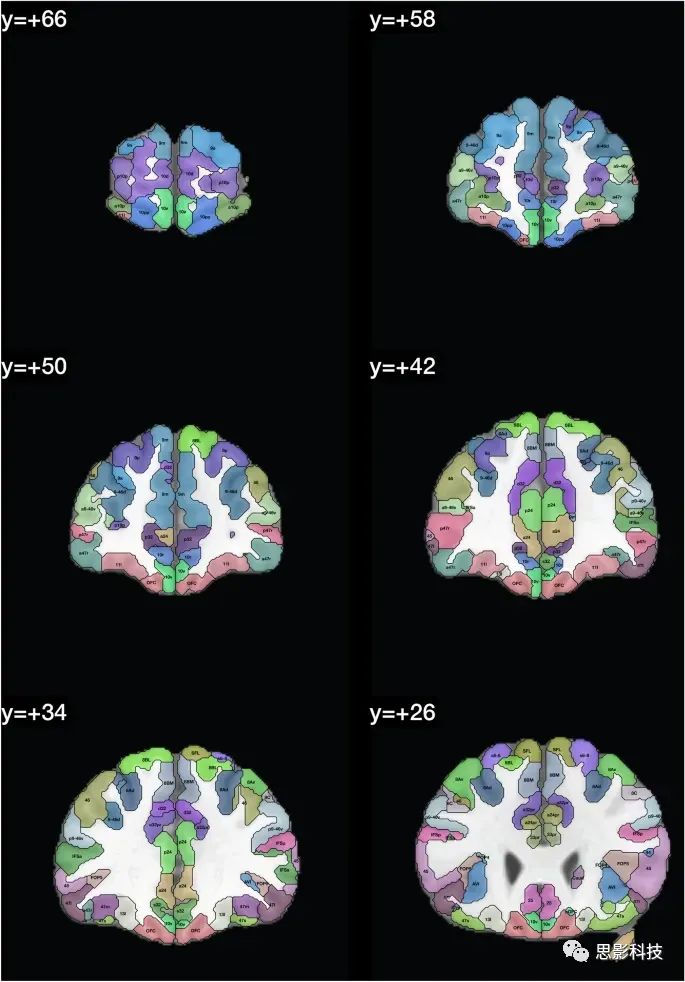

在人类连接组计划(HCP)图谱中区域的定义显示在Glasser et al.(2016a, b)的Glasser_2016_Table.xlsx中。这些区域的列表提供在表1中,并且在图1中,我们展示了带有在HCPex图谱中定义的区域标签的冠状切片。图1中的皮层区域是按照人类连接组计划(HCP)图谱(Glasser et al. 2016a)中的定义来的。

图1:展示了HCPex图谱中定义的区域和新增的皮层下区域的示例冠状切片。这些切片中使用的缩写与表1中的相同。这些冠状切片的y轴坐标是根据MNI(蒙特利尔神经学研究所)坐标系统来确定的。

图1提供了扩展HCP图谱的标记版本,以帮助读者识别这些人脑冠状切片中的脑区域。值得注意的是,一些小的脑结构在这些冠状切片中可能显得非常小,因为它们是被8毫米分隔开的(例如隔核就位于MNI坐标y:3–10之间)。表1和表2提供了图谱中脑区域的列表。在这个重新排序的列表中,标签列表提供在HCPex_LabelID.mat中。

本文描述的HCPex图谱扩展了HCP-MMP1图谱(Glasser et al. 2016a),通过增加66个皮下区域,以体积(volume)形式提供以适用于多种类型的神经影像软件,包括SPM,提供带标签的大脑冠状切片以清晰可视化HCPex图谱中定义的皮层和皮下区域(图1),并提供图谱中皮层区域的可选重排序(表1)。我们已经发现,有了这些扩展,HCPex图谱非常有帮助(Huang et al. 2021; Ma et al. 2021; Rolls et al. 2021)。

总之,这里描述的HCPex图谱通过增加66个皮层下区域、以体积(Volume)形式提供以适用于多种类型的神经影像软件(包括SPM)、提供带标签的大脑冠状切片以清晰可视化HCPex图谱中定义的皮层和皮层下区域(图1)以及提供图谱中皮层区域的可选重排序(表1),从而扩展了HCP-MMP1图谱(Glasser et al. 2016a)。